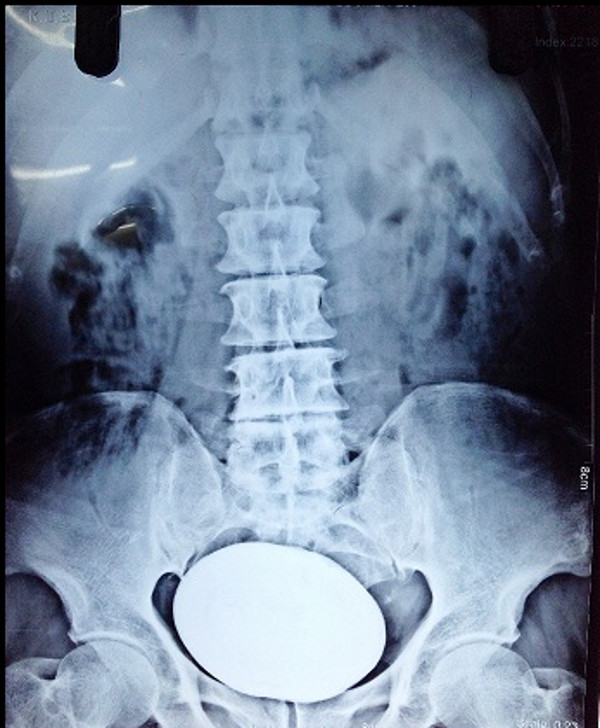

De acordo com médicos de um hospital em Anantnag, nas proximidades de Srinagar (Índia), um cálculo de 834 gramas foi retirado da bexiga de um paciente.A pedra seria um novo recorde mundial.

A pedra retirada estava em Mohammad Yousuf Khan, de 65 anos. Ela está sendo considerada um recorde por conta de seu peso e tamanho.

O objeto retirado mede 15x13 centímetros. O paciente ficou em repouso mas se recupera bem.